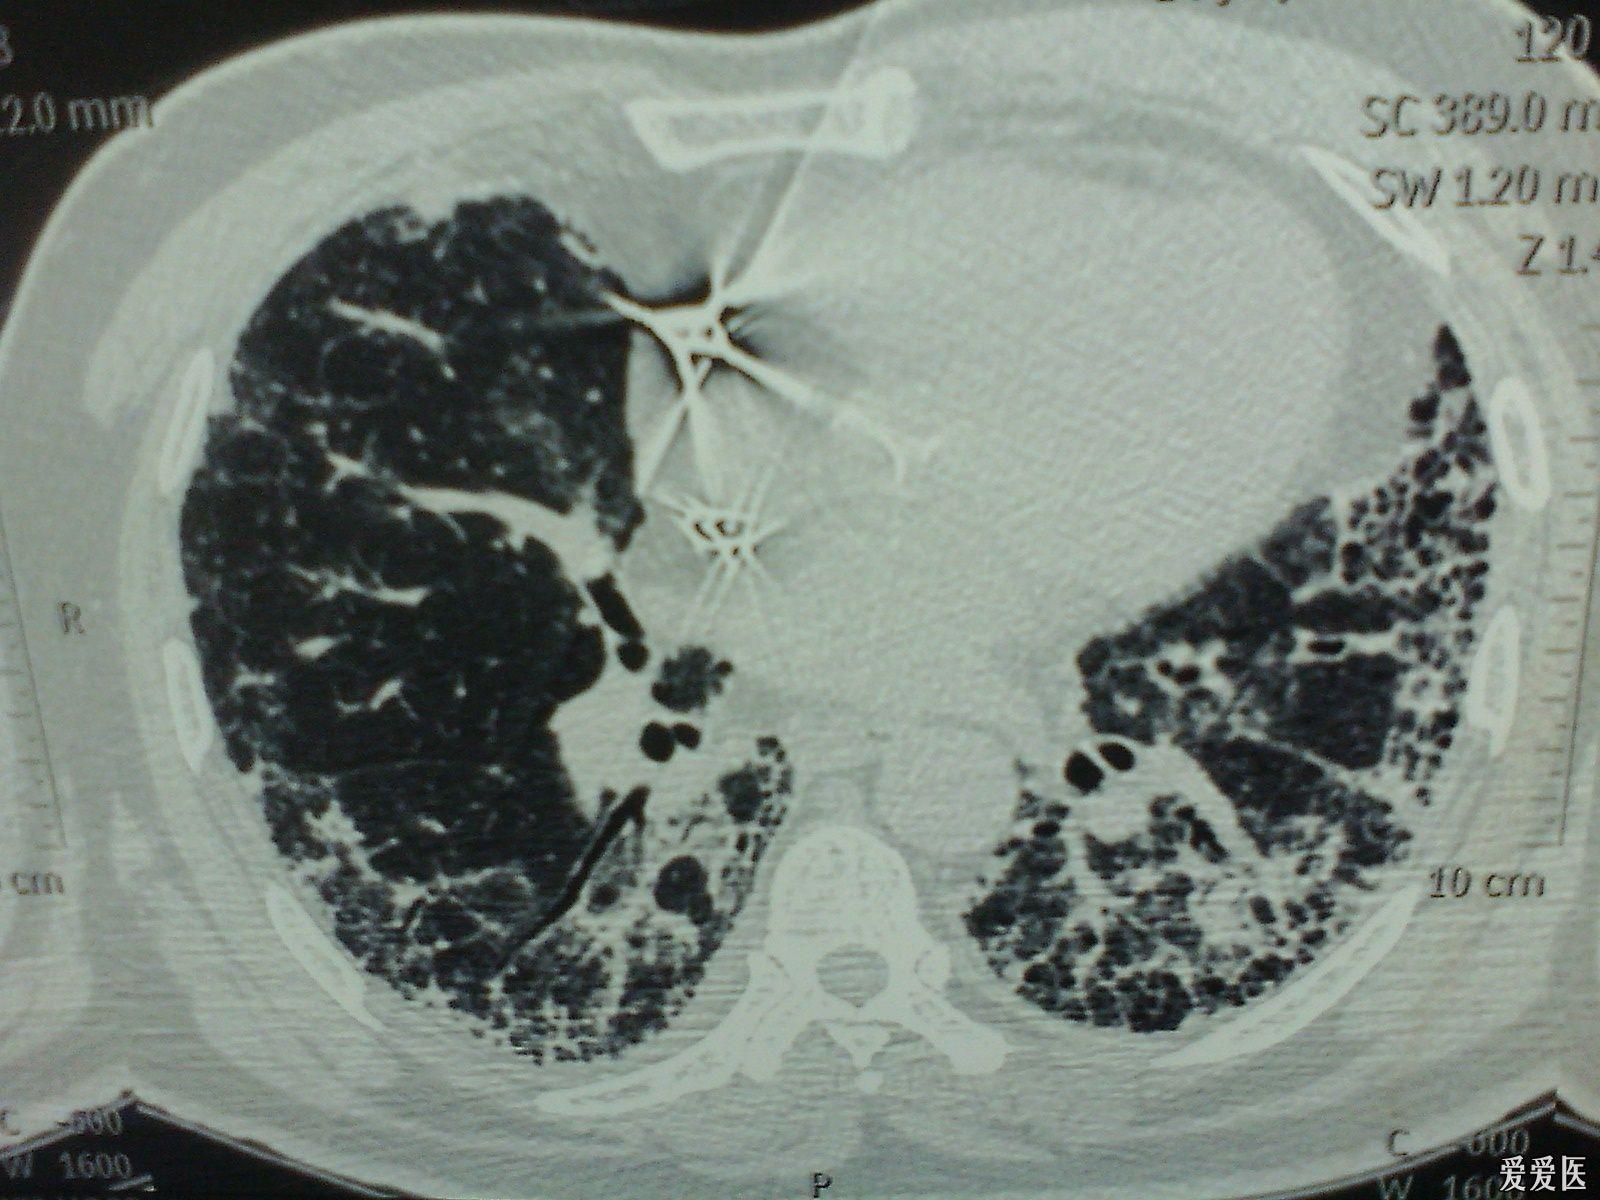

肺纤维化是以成纤维细胞增殖及大量细胞外基质聚集并伴炎症损伤、组织结构破坏为特征的一大类肺疾病的终末期改变,也就是正常的肺泡组织被损坏后经过异常修复导致结构异常(疤痕形成)。绝大部分肺纤维化病人病因不明(特发性),这组疾病称为特发性间质性肺炎(IIP),是间质性肺病中一大类。而特发性间质性肺炎(IIP)中最常见的以肺纤维化病变为主要表现形式的疾病类型为特发性肺更多>>